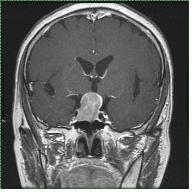

뇌하수체 선종은 원발성 뇌종양의 약 15~20%를 차지하는 양성종양으로, 주로 성인에서 발생하며 여자에게 더 많이 발생하는 종양입니다. 뇌하수체란 뇌의 정중앙부 하단에 위치한 신체기관으로, 주 기능은 다양한 호르몬의 분비입니다. 이 호르몬들은 직접 신체에 영향을 미치거나 타 장기에 있는 호르몬샘의 기능을 조절하게 되어 전체적으로 우리 몸의 호르몬 분비를 총괄하게 됩니다.

뇌하수체 선종은 종양의 크기가 10mm를 넘었는지에 따라 거대선종과 미세선종으로 구분할 수 있으며, 종양의 호르몬 분비 여부에 따라 기능성 뇌하수체 선종과 비기능성 뇌하수체 선종으로 분류할 수 있습니다. 호르몬의 과다분비로 인한 기능성 선종의 경우 미세선종이 흔하며 대부분 호르몬 과다분비에 따른 증상으로 발견됩니다. 비기능성 종양의 경우 거대선종인 경우가 많고 시신경 압박에 의한 시력 감퇴와 시야 축소 또는 두통 등의 증상으로 발견됩니다.